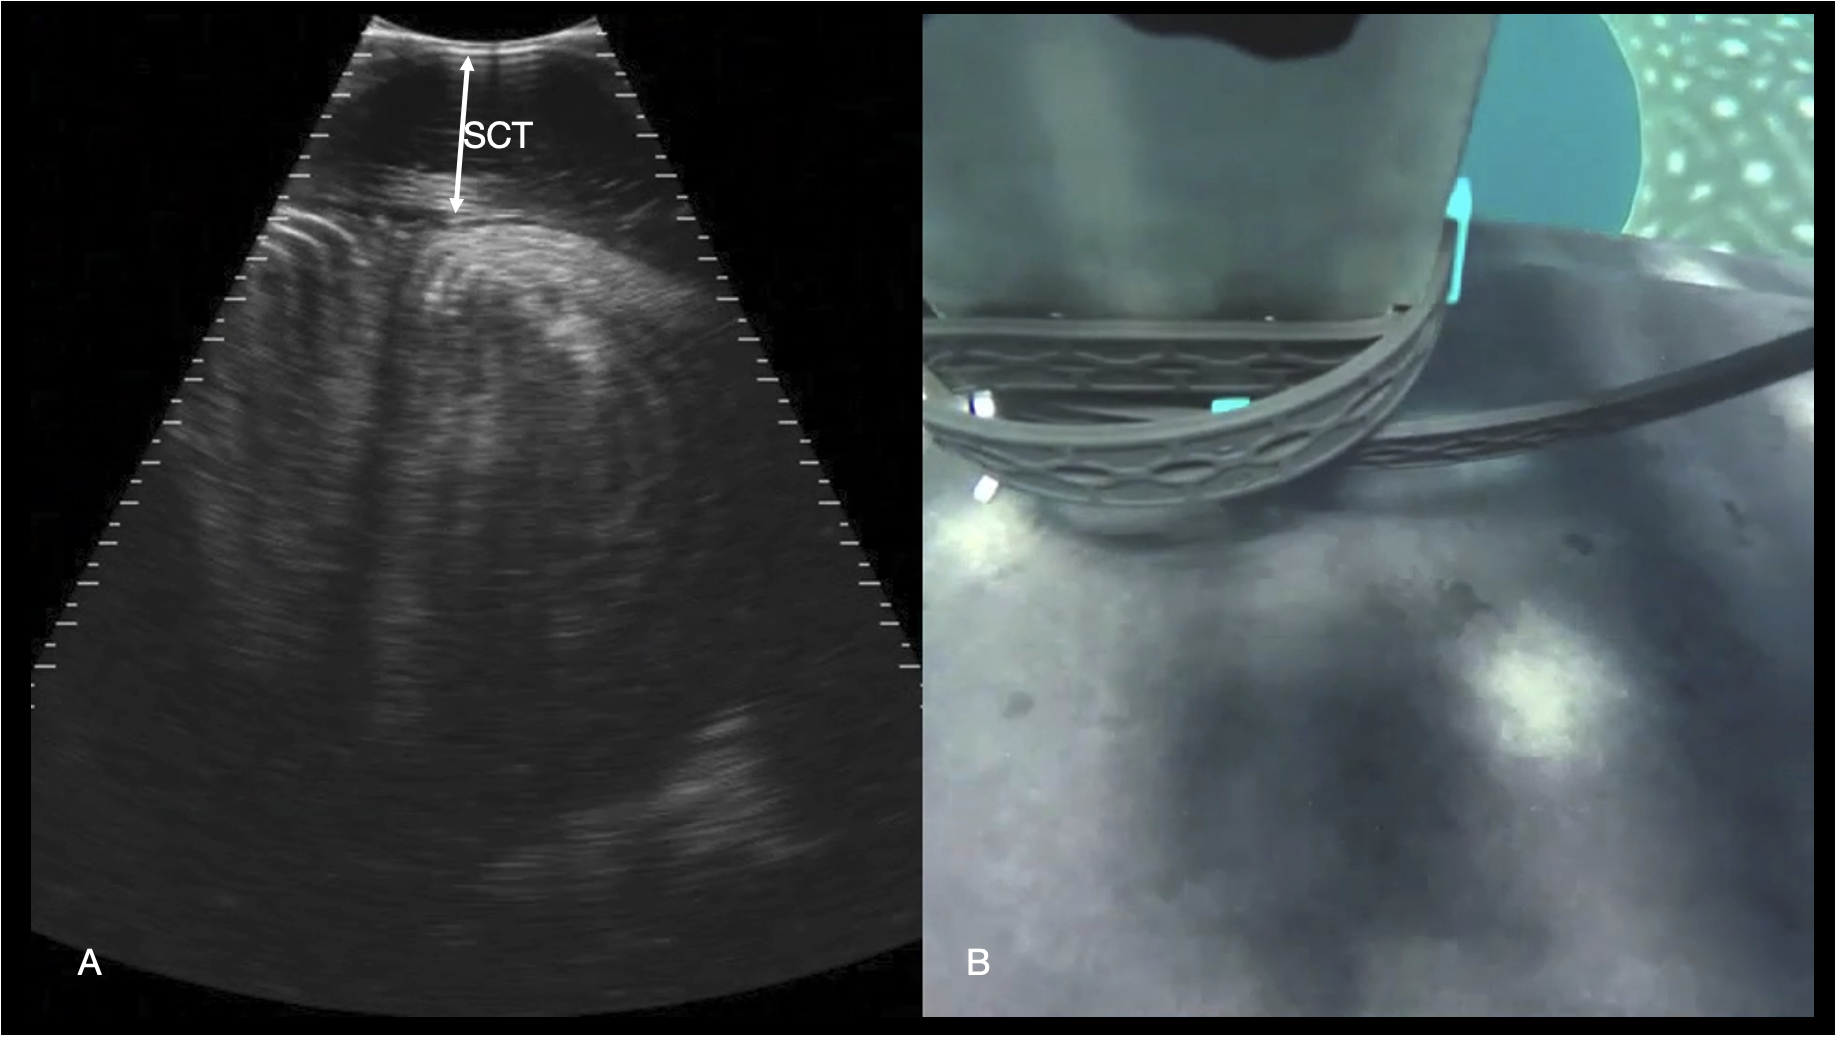

Figure 11

Epaxial musculature. (A) Transverse right paramedian sonogram of the dorsal myomeres just caudal to the pectoral fins. The subcutaneous connective tissue (SCT) depth is marked with an arrow. Displayed depth is 21 cm, left of the animal is to the left of the image. See video S9. (B) Synchronized GoPro image of the transducer position for the sonogram in (A) The left pectoral fin is visible in the top right-hand corner of the image, and the midline spinal ridge visible just in front of the transducer.

Dorsal body

The paraspinal musculature was imaged at several points along the dorsum (caudal to the gills, parasagittal caudal to the dorsal fin and along the mid lateral back). In the transverse plane the roughly rectangular myomeres were identified with concentric hyperechoic lamellae (Figure 11). The thickness of the connective tissue deep to the skin was readily distinguished on the images but appeared to vary according to the anatomic site and as the position of image acquisition was not standardized in this initial study, connective tissue thickness was not recorded.